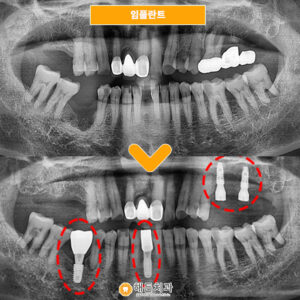

더불어 왼쪽 위턱 기존에 상실되어 있던

첫 번째 어금니 부위도 함께

임플란트를 진행하였는데요.

치아가 상실되지 시간이 많이 흘렀다 보니

인접치인 두 번째 어금니가

앞쪽 빈자리로 살짝 기울어져 있었습니다.

이대로 임플.란트를 식립하게 될 경우

큰 어금니 자리에

작은 어금니 크기의 보철물이 올라가게 되어

제대로 씹.는 기능을 못하는 경우도 있고,

비 심미적으로 보일 수도 있습니다.

그래서 공간 확보를 위해

두 번째 어금니 치아머리 부분을

조금 다듬었는데요.

치아머리 부분을 삭제하였기에

약해진 치아를 보호하기 위해서

크라운을 씌워주었고

덕분에 첫 번째 어금니 자리에도

임플.란트와 알맞은 크기의

크라운이 올라갈 수 있었습니다.

♥ 치료 전/후 ♥

(2024.01.25 ㅡ> 2024.06.10)

2개의 부위 모두

임플란트 식립을 완료한 모습입니다.